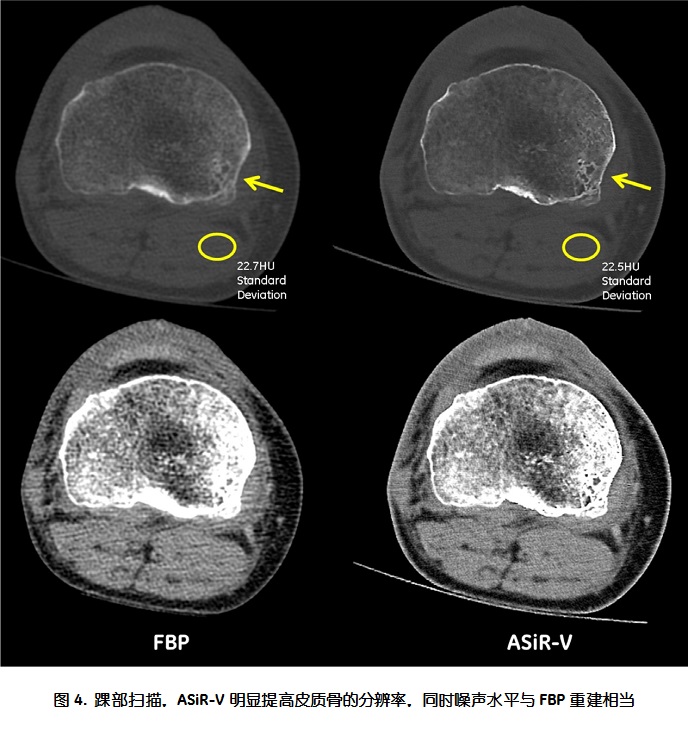

传统的迭代重建算法在降低噪声的时候,往往会导致图像空间分辨率的降低。ASiR-V由于在迭代过程中纳入了被扫描物体模型和物理模型,在降低剂量的同时可以保持空间分辨率不变;在相同的剂量条件下,与FBP相比,ASiR-V有提高空间分辨率的能力。图4所示一个踝部扫描的病例,在低剂量条件下ASiR-V将图像噪声抑制到与FBP相似的水平,同时明显提高皮质骨的空间分辨率。